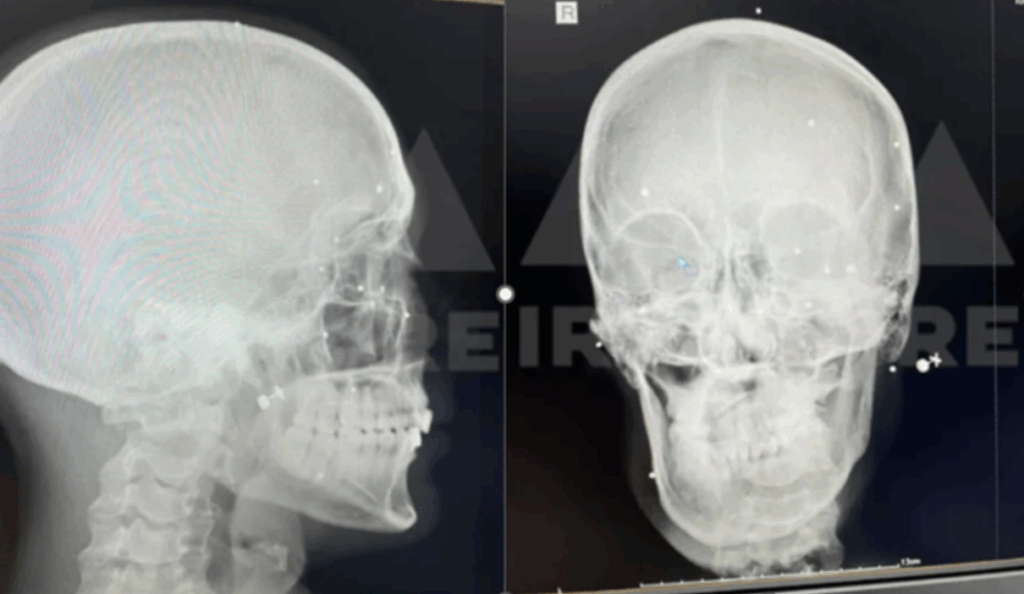

برای تهیه این گزارش، پروندههای پزشکی شماری از آسیبدیدگان چشمی با گروهی از چشمپزشکان متخصص در نقاط مختلف جهان به اشتراک گذاشته شده است. نتایج بررسیها حاکی از آن است، که الگوی آسیبهای چشمی دلالت بر شلیکهای هدفمند دارد. این متخصصان همچنین تأکید کردهاند، که پیامدهای روانی نابینایی با تجربه ابتلا به سرطان قابل مقایسه است، که شدت خسارات جسمی و روانی ناشی از این نوع سرکوب را بهروشنی نشان میدهد.

پروندههای پزشکی شمار زیادی از قربانیانی که بر اثر اصابت گلولههای ساچمهای به سر و چشم مجروح شدهاند، نشان میدهد که شلیک از فاصله نزدیک انجام گرفته است. یکی از این موارد، حسین، مردی میانسال است که هر دو چشم خود را از دست داد و برای همیشه نابینا شد. در پرونده پزشکی او وجود دستکم ۳۰۰ ساچمه در اطراف چشمهایش ثبت شده است. در زمان حادثه، او به همراه همسرش در مراسم چهلم حدیث نجفی در کرج شرکت کرده بود. شواهد پزشکی و روایتهای شاهدان نشان میدهند، که حسین در حالی که بیحرکت بر زمین افتاده و تسلیم شده بود، با شلیک تفنگ شاتگان هدف قرار گرفت.[۹۴] حسین به دلیل نگرانی از انتقامجویی حکومت ایران ترجیح داده است، که هویت خود را ناشناس نگه دارد.